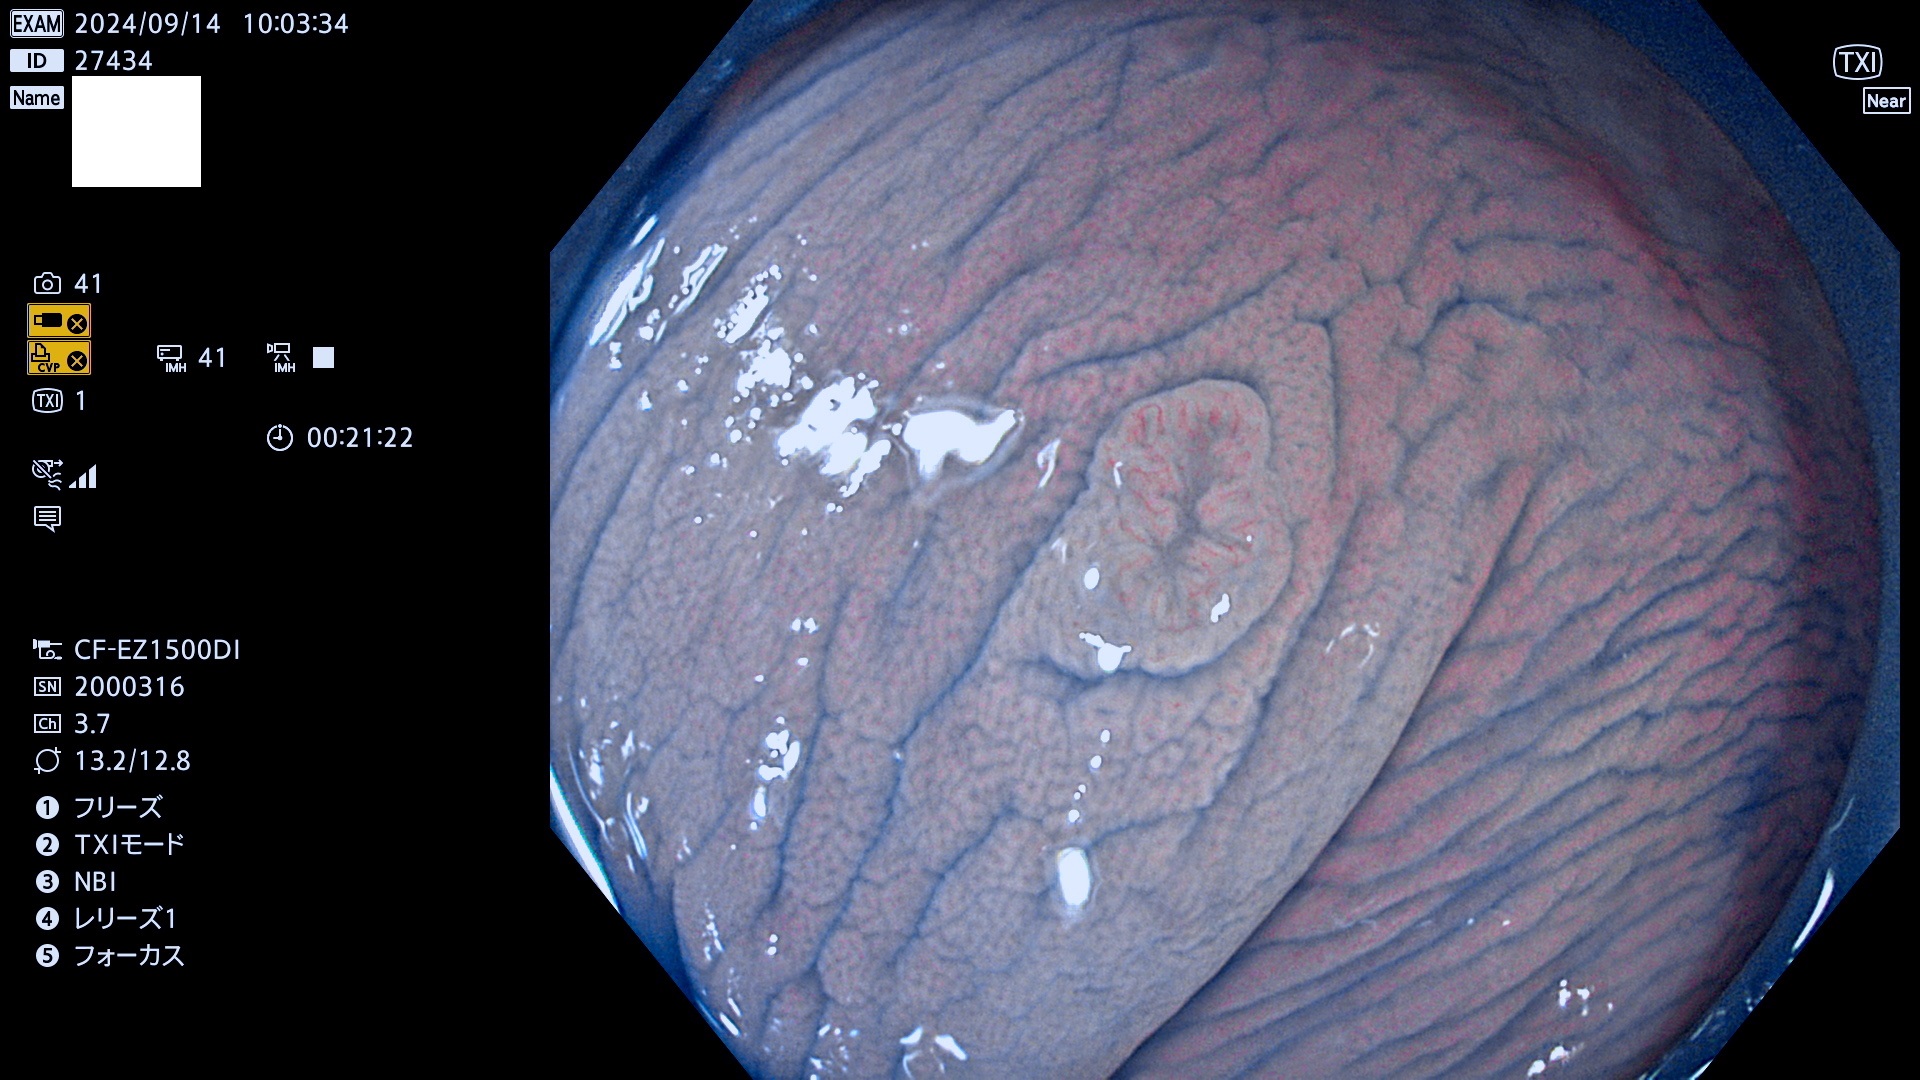

完全に平坦な物をUb、陥凹している物をUcと呼びます。最も発見が難しく危険な病変です。

毎週の検査(木・金・土・日)に発見されたUb、Uc型・腺腫を、その週の日曜の夜にUPし1週間、提示します。

抽出の対象期間 2024年9月12日〜9月15日の4日間(45件の検査)9件 (9/45=20%)